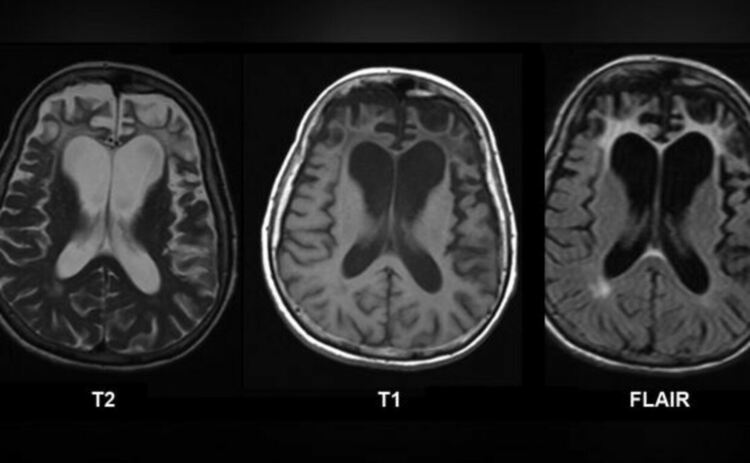

На 24-годишна възраст повечето мозъци все още се адаптират към зряла възраст. Но мозъкът на Ярхам изглеждаше с десетилетия по-възрастен - наподобяващ мозък на 70-годишен , според ЯМР сканирането, което помогна за диагностицирането на болестта.

Сканирания на мозъка, проведени докато Ярхам е бил жив, показват поразително свиване за човек на толкова млада възраст. Но сравняването на мозъка на Ярхам с този на някой на около 70 години би било подвеждащо. Мозъкът му не е „остарял по-бързо“ в обичайния смисъл. Вместо това, голям брой неврони са били загубени за кратък период от време поради болестта.

При здравословно стареене мозъкът се променя бавно. Някои области стават малко по-тънки, но цялостната структура остава непокътната в продължение на десетилетия. Но при агресивни форми на деменция, цели мозъчни мрежи се разпадат бързо.

При фронтотемпоралната деменция, фронталният и темпоралният лоб могат да се свият драстично. С влошаването на състоянието на тези области, хората губят способностите, които тези области поддържат – включително реч, емоционален контрол и способности за вземане на решения. Това би обяснило защо Ярхам е загубил говора си толкова късно, но толкова внезапно – и защо нуждата му от грижи на пълен работен ден ескалира толкова бързо.